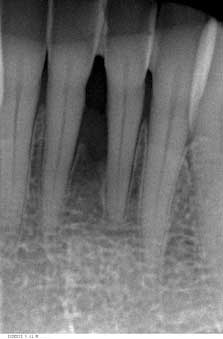

Veröffentlicht 12. März 2009 am 223 × 339 in Projektion und Ausmaß von ossären Läsionen – Täuschung und Realität